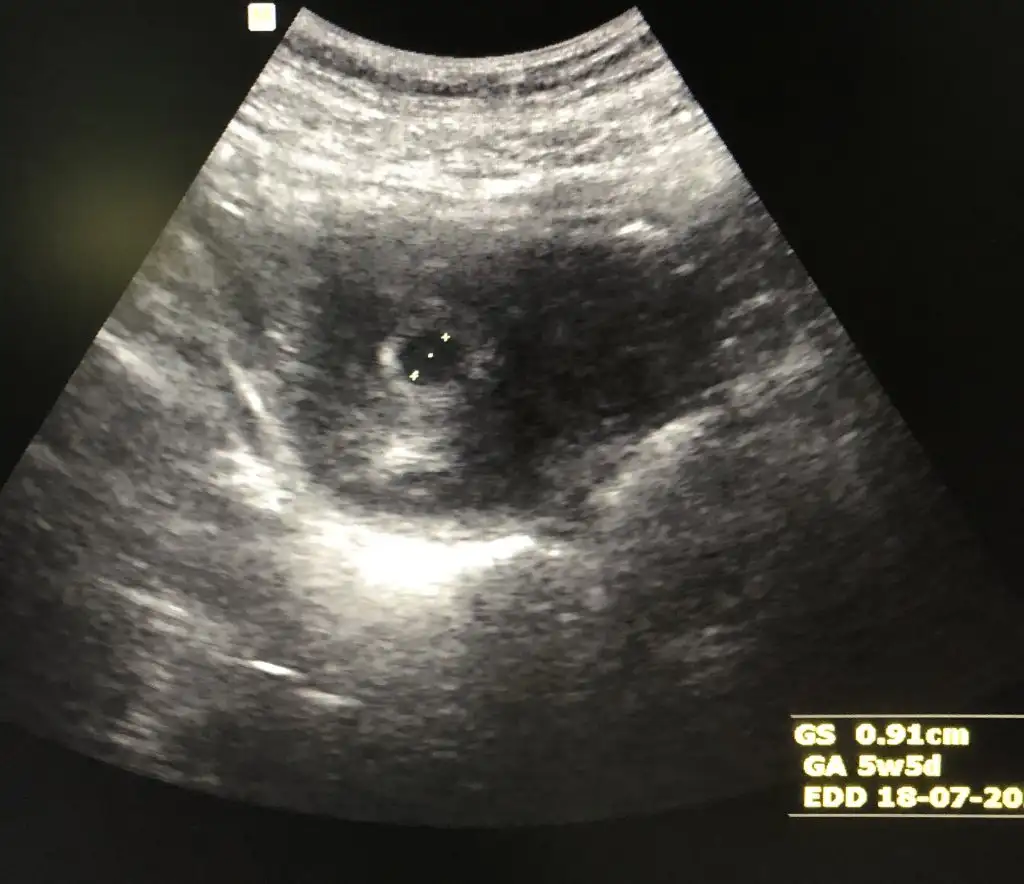

Keseye göre karından bakıldıysa erkekGerçekten miii☺☺ Bir de 8. Hafta ve 6. Hafta var. Kaybolan ikiz sendromu yaşadığım için doktor 1 ay sonra gelin demişti. O yüzden 12. Hafta var.onları da ekleyeyim.

Evet hepsi karından bakıldı. Erkek hissediyorum ben deKeseye göre karından bakıldıysa erkek

İlk bebekmiEvet hepsi karından bakıldı. Erkek hissediyorum ben deçok teşekkür ederim kesinleşince yazarım buraya